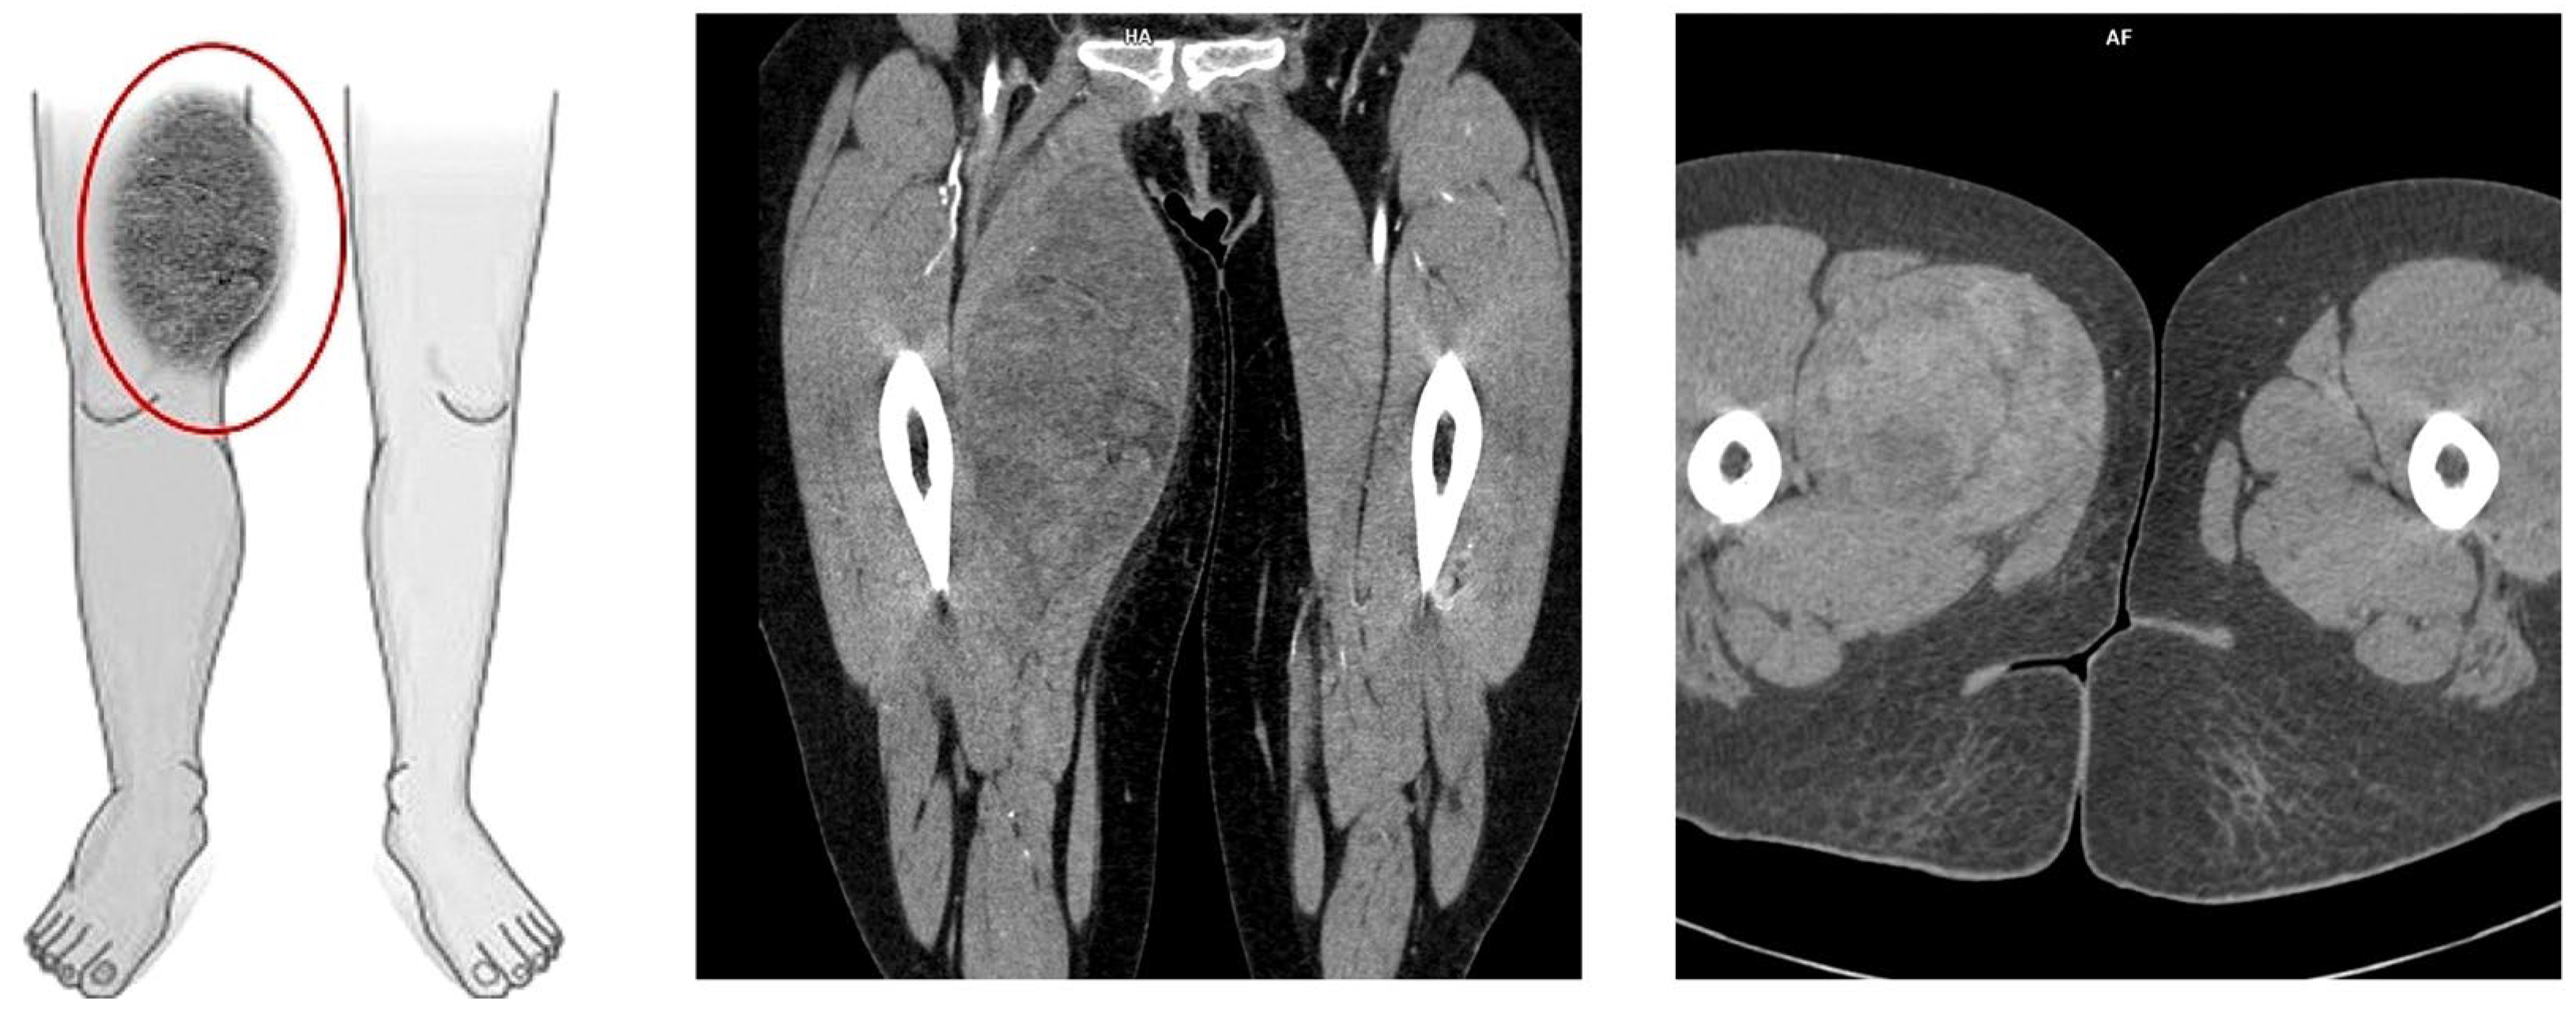

On the 11th day of the puerperium, the patient presented at the gynecology ward again during overnight hours due to the sudden appearance of a tumor in the medial part of the right thigh. The lesion was non-painful, mobile, soft, approximately 20 cm in diameter, and protruded above the level of the rest of the thigh surface. It was not accompanied by visible skin lesions. Owing to the sudden onset and clinical presentation of the lesion, a preliminary diagnosis of soft-tissue hematoma during the rupture of a venous vessel was made. An ultrasound examination (GE Voluson S10 Expert; BT16, 2019; convex 3/4D RAB6-RS transducer; General Electric Company, Schenectady, USA) showed an oval, focal, and confined space of variable echogenicity, measuring 15.74 × 8.59 cm, with a superficial localization involving the soft tissues of the right thigh and the lower pole reaching the quadriceps muscle (Figure 1).

Figure 1.

Ultrasound image of right thigh tumor (GE Voluson S10 Expert; BT16, 2019; 3/4D convex probe RAB6-RS) Red circle- tumor.